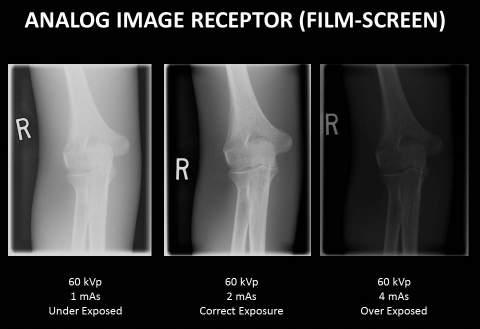

Image Quality in Film-Screen (Analog) Radiography Exposure factors, 36

Image Quality in Digital Radiography Exposure factors, 47 Image quality factors, 48 • Brightness, 48 • Contrast resolution, 48 • Spatial resolution, 49 • Distortion, 49 • Exposure indicator, 49 • Noise, 50 Post-processing, 51